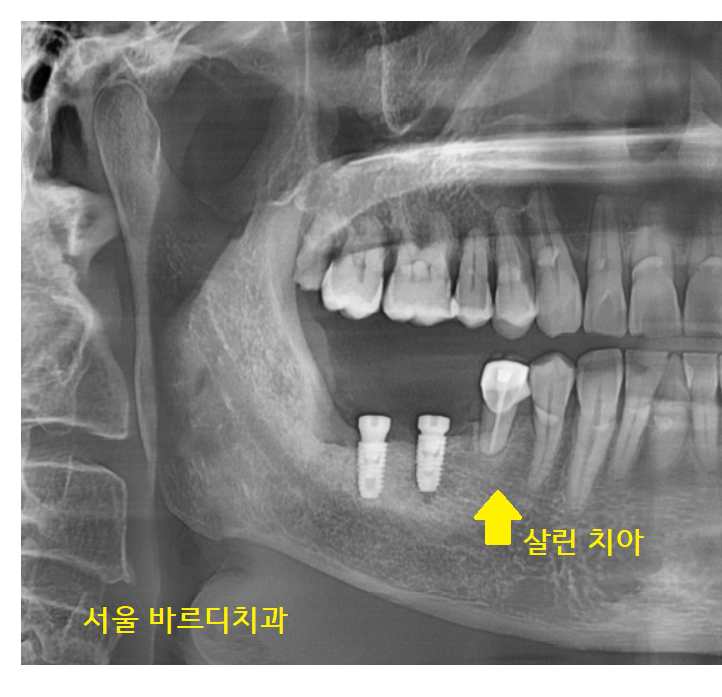

강일역 치과를 방문해 주신 환자분 사진입니다.

아... 큰 사진에서도

문제 치아를 바로 발견했는데요.

23.02.08

오래전 브릿지로 씌워둔 치아가

수명을 다했네요.

잇몸뼈가 많이 녹아서

뿌리 끝부분만 붙잡고 있는 게 보이시죠~?

보철물 아래쪽으로 음식물도 끼고

불편하셨겠어요.

3개의 보철 중

작은 어금니 치아는 살려볼 수 있었는데요.

자연 치아가 1개라도 더 있으면 유리하기 때문에

오래된 브릿지를 잘라서

부분 임플란트 하기로 상담해 드렸습니다.